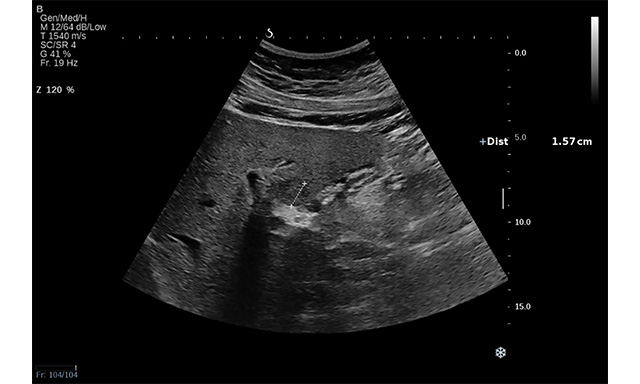

Another aspect that must be considered is the infiltrative pattern of HCC associated with an increased risk of surveillance failure compared to the nodular type (57.1% vs. 2.1%; P < 0.001)[28]. Noteworthy, advanced HCC may coexist with a macrovascular invasion. Based on the thrombus echogenicity, US cannot differentiate between malignant and benign thrombus. Even though Colour Doppler can detect the presence of vessels, indicating malignity, the method’s sensitivity is lower than 20%[29] [Figure 4A and B]. Thus, US visualisation of macrovascular thrombosis requires further imaging with contrast agents.

Figure 4. Thrombosis of portal vein (main, right and left branch) in a 62-year-old man recently diagnosed with NASH-related cirrhosis in B mode (A) and Doppler mode (B).